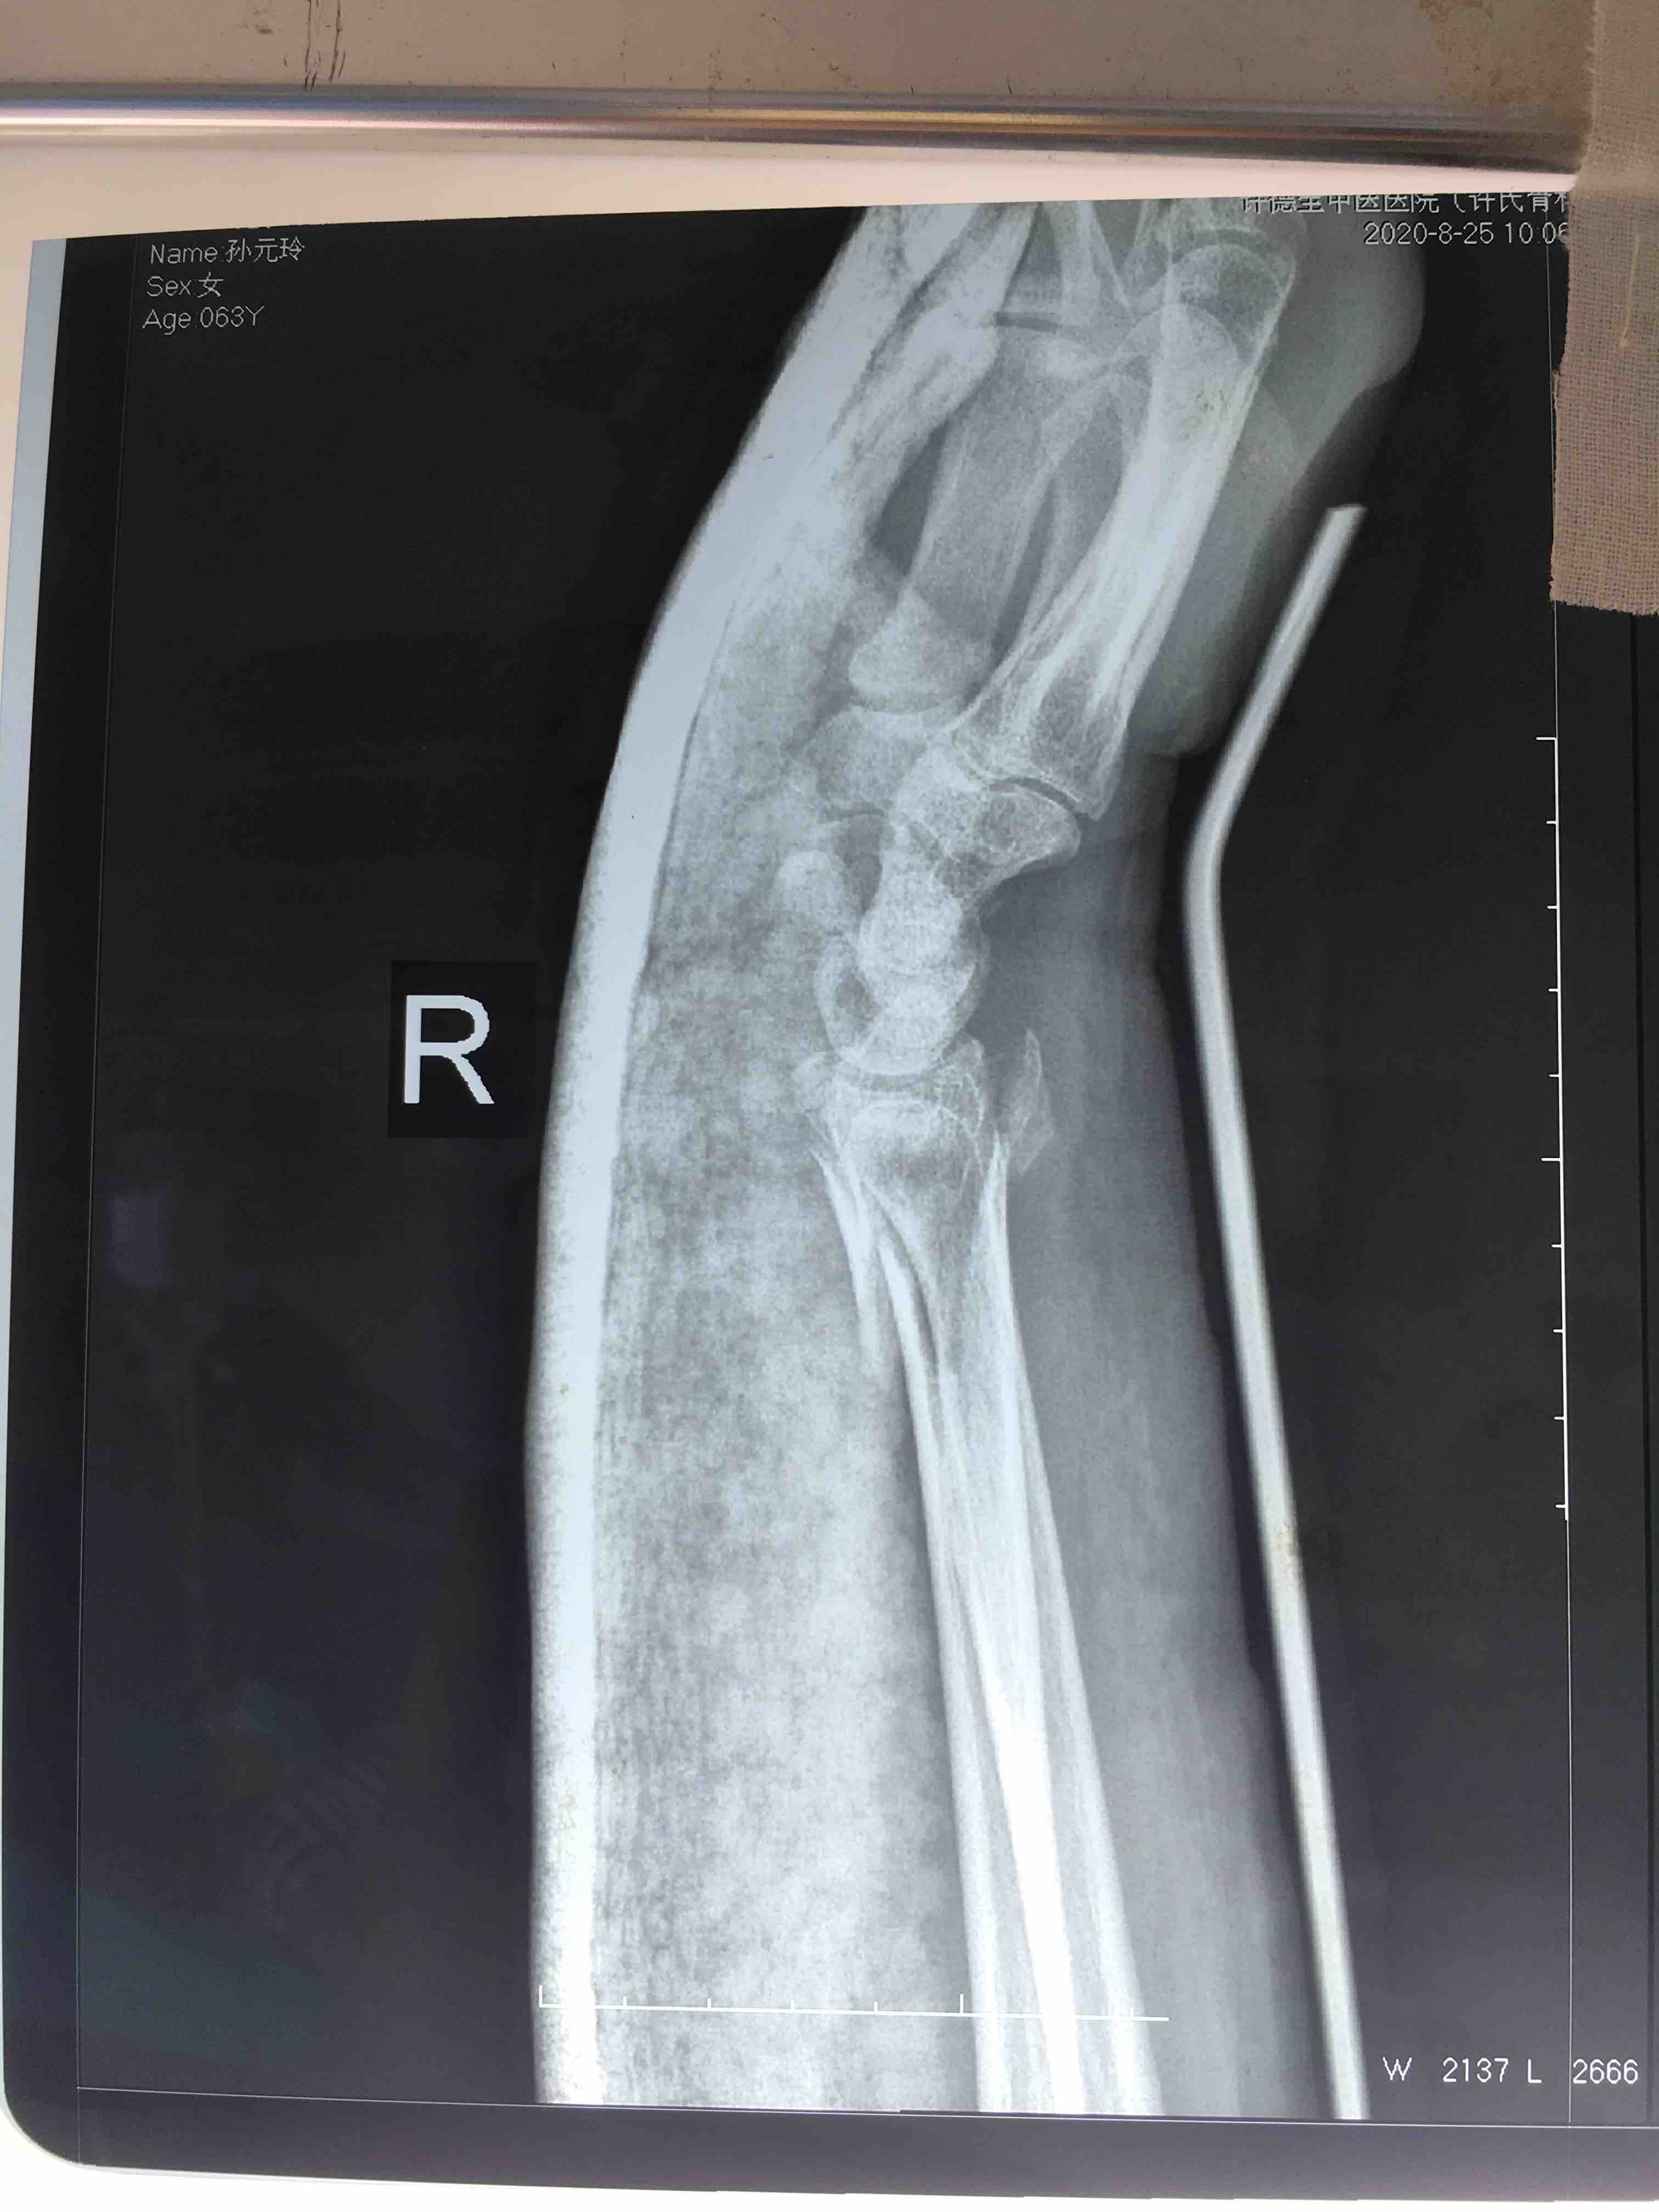

斯密斯骨折(保守治疗失败一例)

摔伤后右腕肿痛,畸形1小时入院。既往身体健康,无特殊不良嗜好。

右腕部肿胀明显,畸形,局部皮色皮温正常,压痛及纵向叩击痛阳性,活动受限,末梢血运感觉正常。

切开复位内固定术,术后抗炎,消肿等处理。